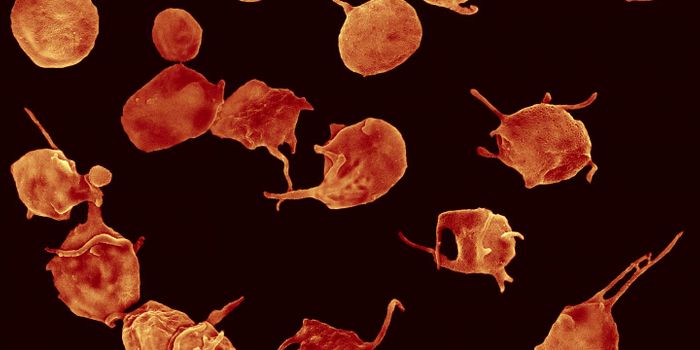

NOV 09, 2017CardiologyBlood clots are normally seen as something to be avoided, something with dangerous consequences such as heart attack, st ...

SEP 17, 2020Clinical & Molecular DXBlood clotting, also known as coagulation, is a critical biological mechanism to prevent excessive blood loss in the eve ...

MAY 25, 2017CardiologyThe development of a blood clot could be very beneficial or very dangerous, depending on the situation. On one ha ...